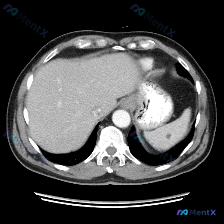

今天整理了一张很有启发的上腹部CT平扫影像,核心发现是脾脏内的多发类圆形低密度灶,想和大家一起梳理一下鉴别诊断的思路。 --- 先看影像的客观表现 这是一张上腹部横断面CT平扫(软组织窗): - 肝脏:形态大小、实质密度都还好,没看到明确占位,肝门血管也清晰; - 脾脏:是最显眼的地方——多个类圆形...